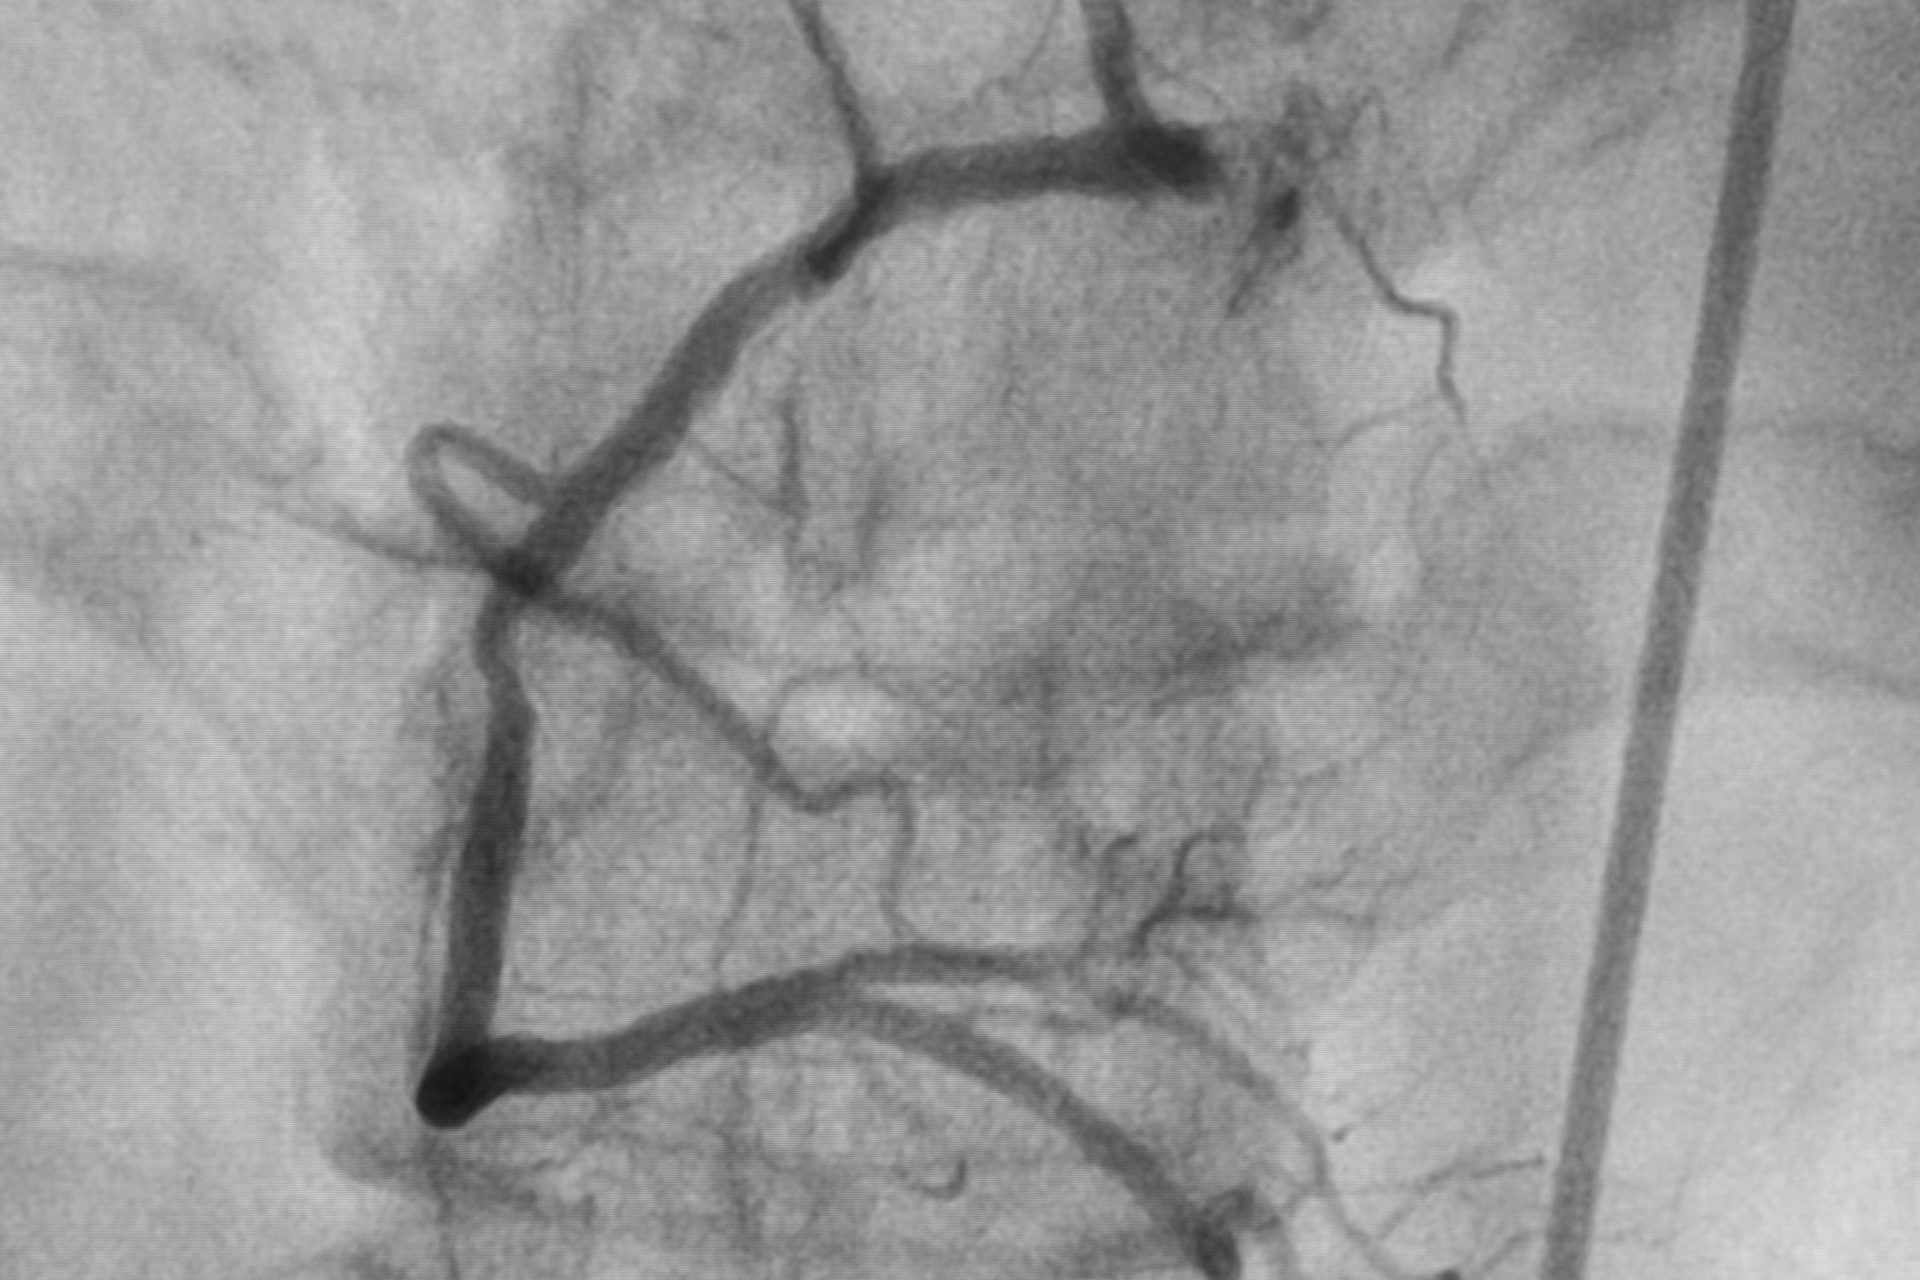

A dye is first introduced into the patient’s heart through a catheter inserted from the limb. X-rays are then taken as the dye moves through the heart to assess pressure and oxygen content in the cardiac chambers and the heart’s pumping ability.

The dye shows up as white lines on the X-rays, with disruption or narrowing of the lines indicating areas where the coronary arteries are obstructed.